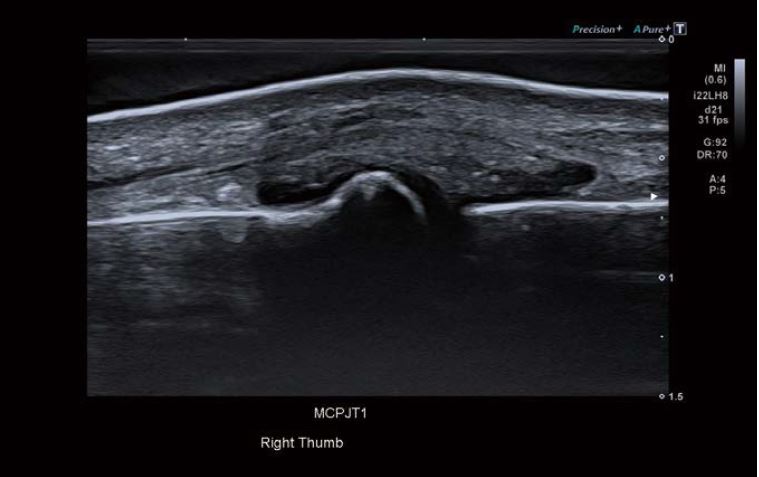

Зображення 1 Знімок суглоба хрестоподібного відростка чітко демонструє рідину, що витікає з суглоба.